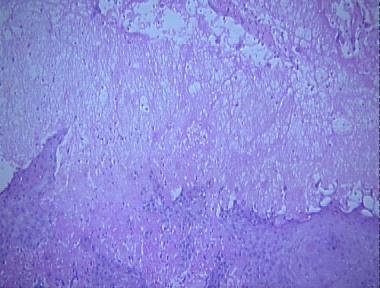

Histologic Features

- A scale-crust

- A multiloculated intraepidermal vesicle involving the upper epidermis

- Marked epidermal hyperplasia

- Ballooning degeneration of the upper keratinocytes with intranuclear eosinophilic inclusion bodies

- Extensive reticular degeneration of the blister space containing numerous eosinophils, neutrophils and a few lymphocytes

- Marked edema of the papillary dermis

- A dense diffuse mixed cell infiltrate consisting of lymphocytes, histiocytes, neutrophils, eosinophils, and plasma cells in the dermis

- Telangiectatic vessels